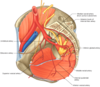

Gluteus maximus

- illium, sacrum, coccyx, sacrotuberous lig–> gluteal tuberosity of femor and illiotibial track

- inferior gluteal nerve L5-S2

- actions

- forceful extension of hte hip

- external rotation of extended thigh

- stabilixe the exteneded knee